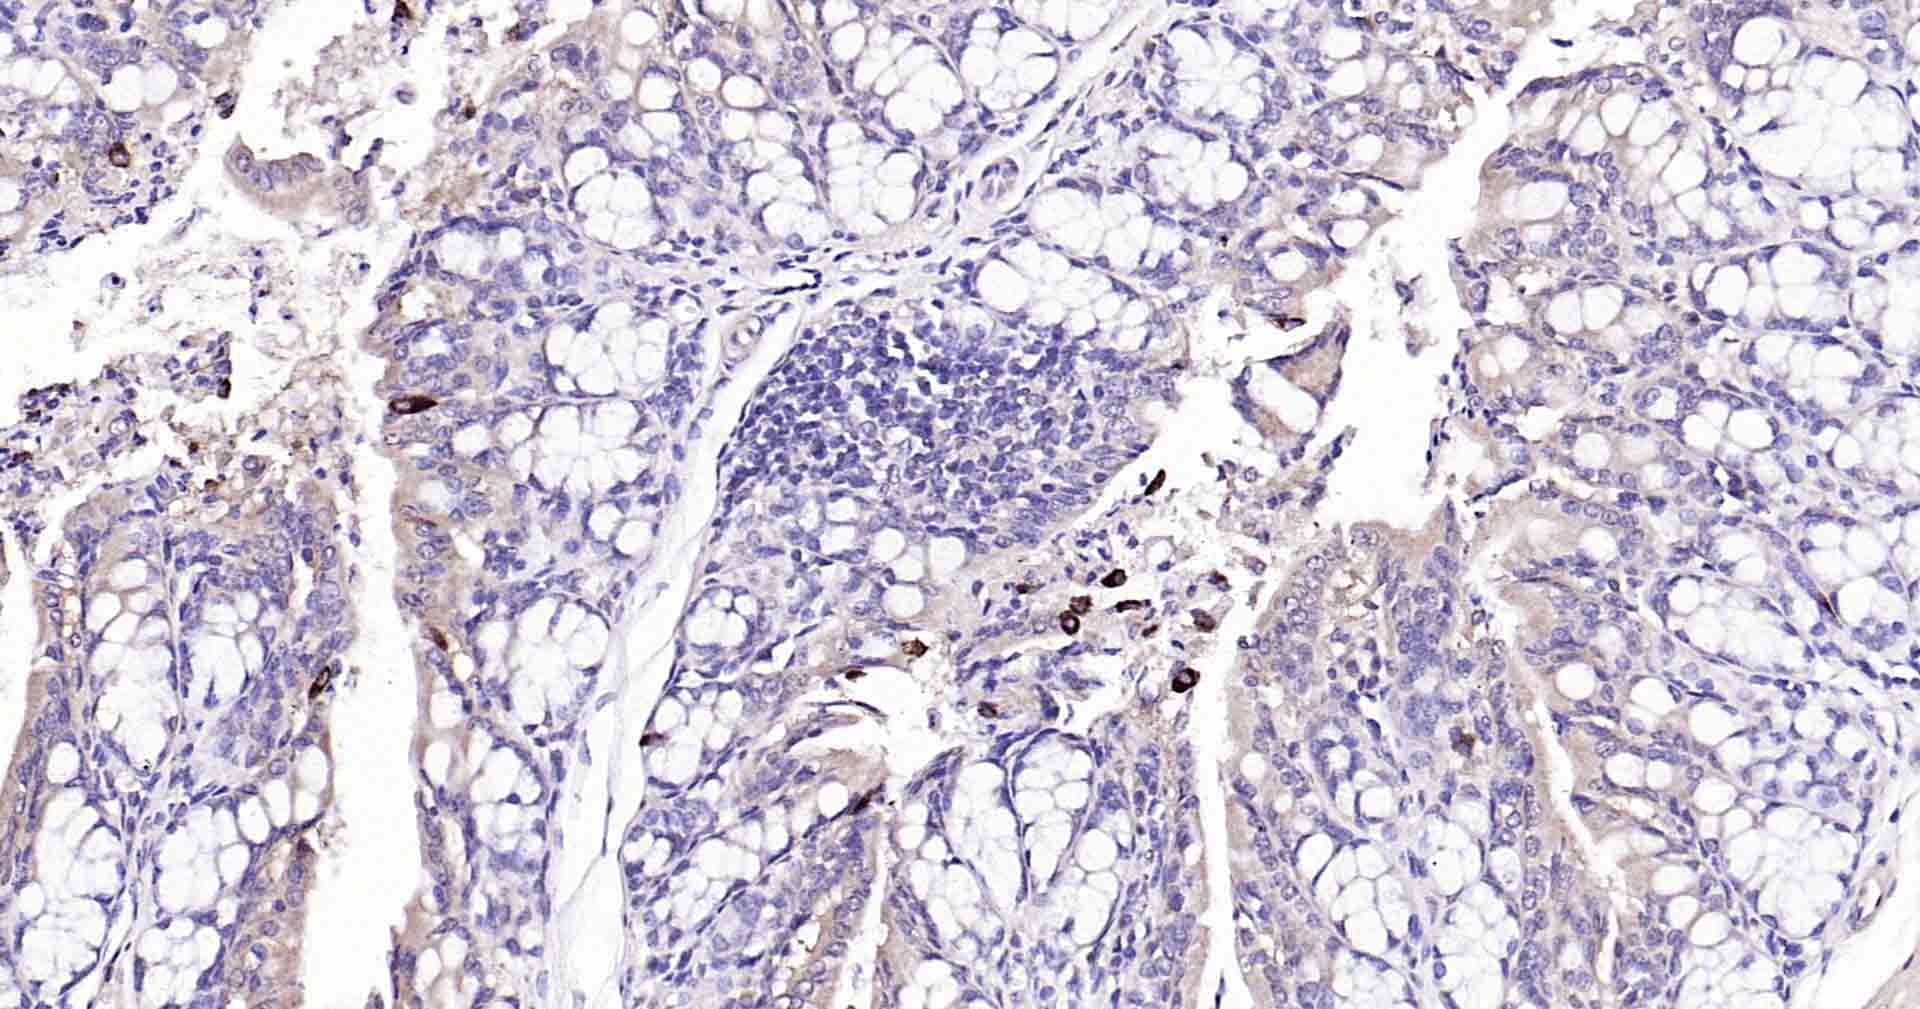

Paraformaldehyde-fixed, paraffin embedded Rat Colon; Antigen retrieval by boiling in sodium citrate buffer (pH6.0) for 15 min; Antibody incubation with Beclin 1 Monoclonal Antibody, Unconjugated(bsm-41365R) at 1:50 overnight at 4°C, followed by conjugation to the SP Kit (Rabbit, SP-0023) and DAB (C-0010) staining.